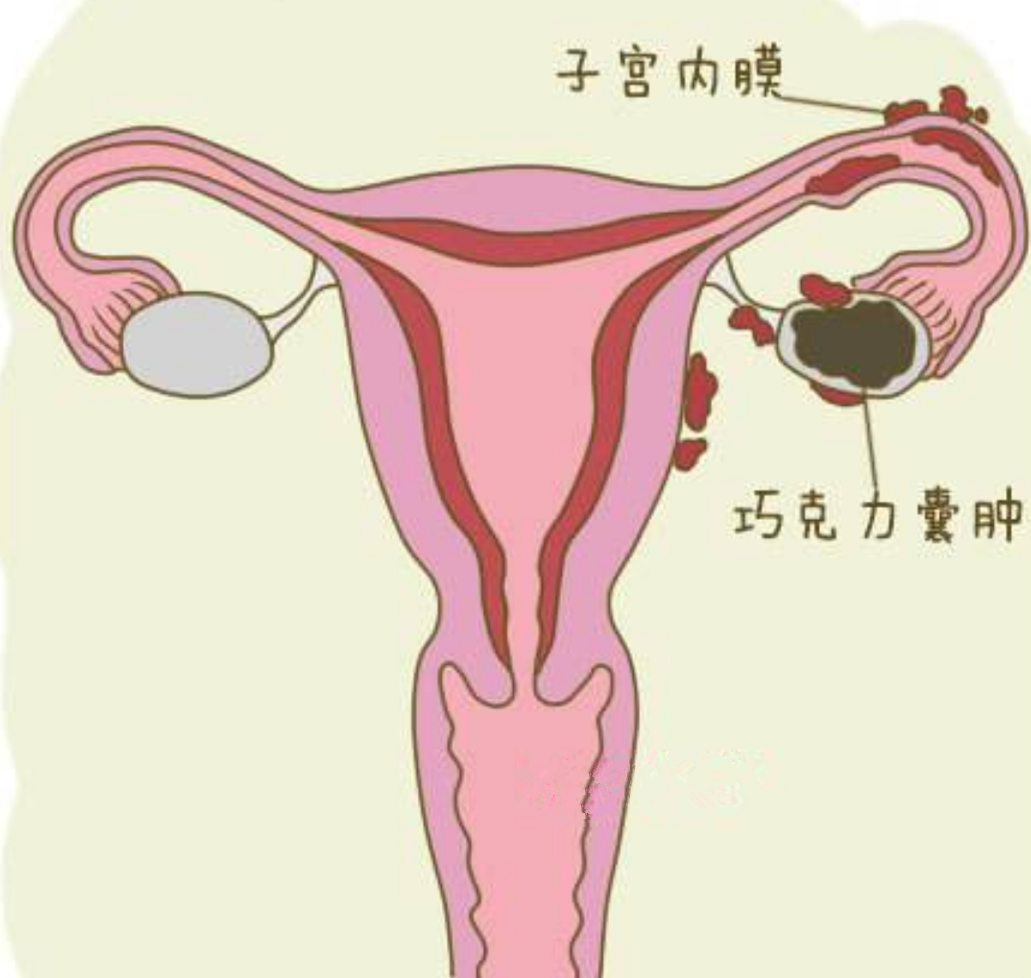

巧克力囊腫圖片

巧克力囊腫

什麼是巧克力囊腫

A:巧克力囊腫也就是卵巢子宮內膜異位囊腫,它是由於異位的子宮內膜在卵巢內生生長,隨著月經多次樣出血,形成了一個存在陳舊性的積血囊腫,囊腫內容物一般像巧克力狀,所以稱為巧克力囊腫。引起內膜異位囊腫的原因現在不清楚,有許多的學說,最常聽到的就是子宮……

A:卵巢巧克力囊腫是子宮內膜異位症的一種,子宮內膜異位症包括巧克力囊腫、盆腔子宮內膜異位結節,以及子宮腺肌症。卵巢巧克力囊腫是經血逆流導致,經期會有經血逆流,如果逆流的經血種植在卵巢表面,定期剝脫、出血,逐漸增大就會形成巧囊,這與女性的特殊體質……